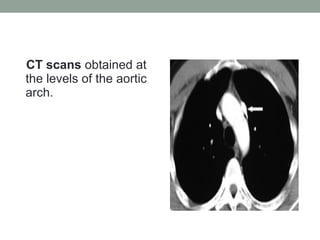

CT scans obtained at

the levels of the aortic

arch.

CT scans obtainedat the levels of the aortic arch.